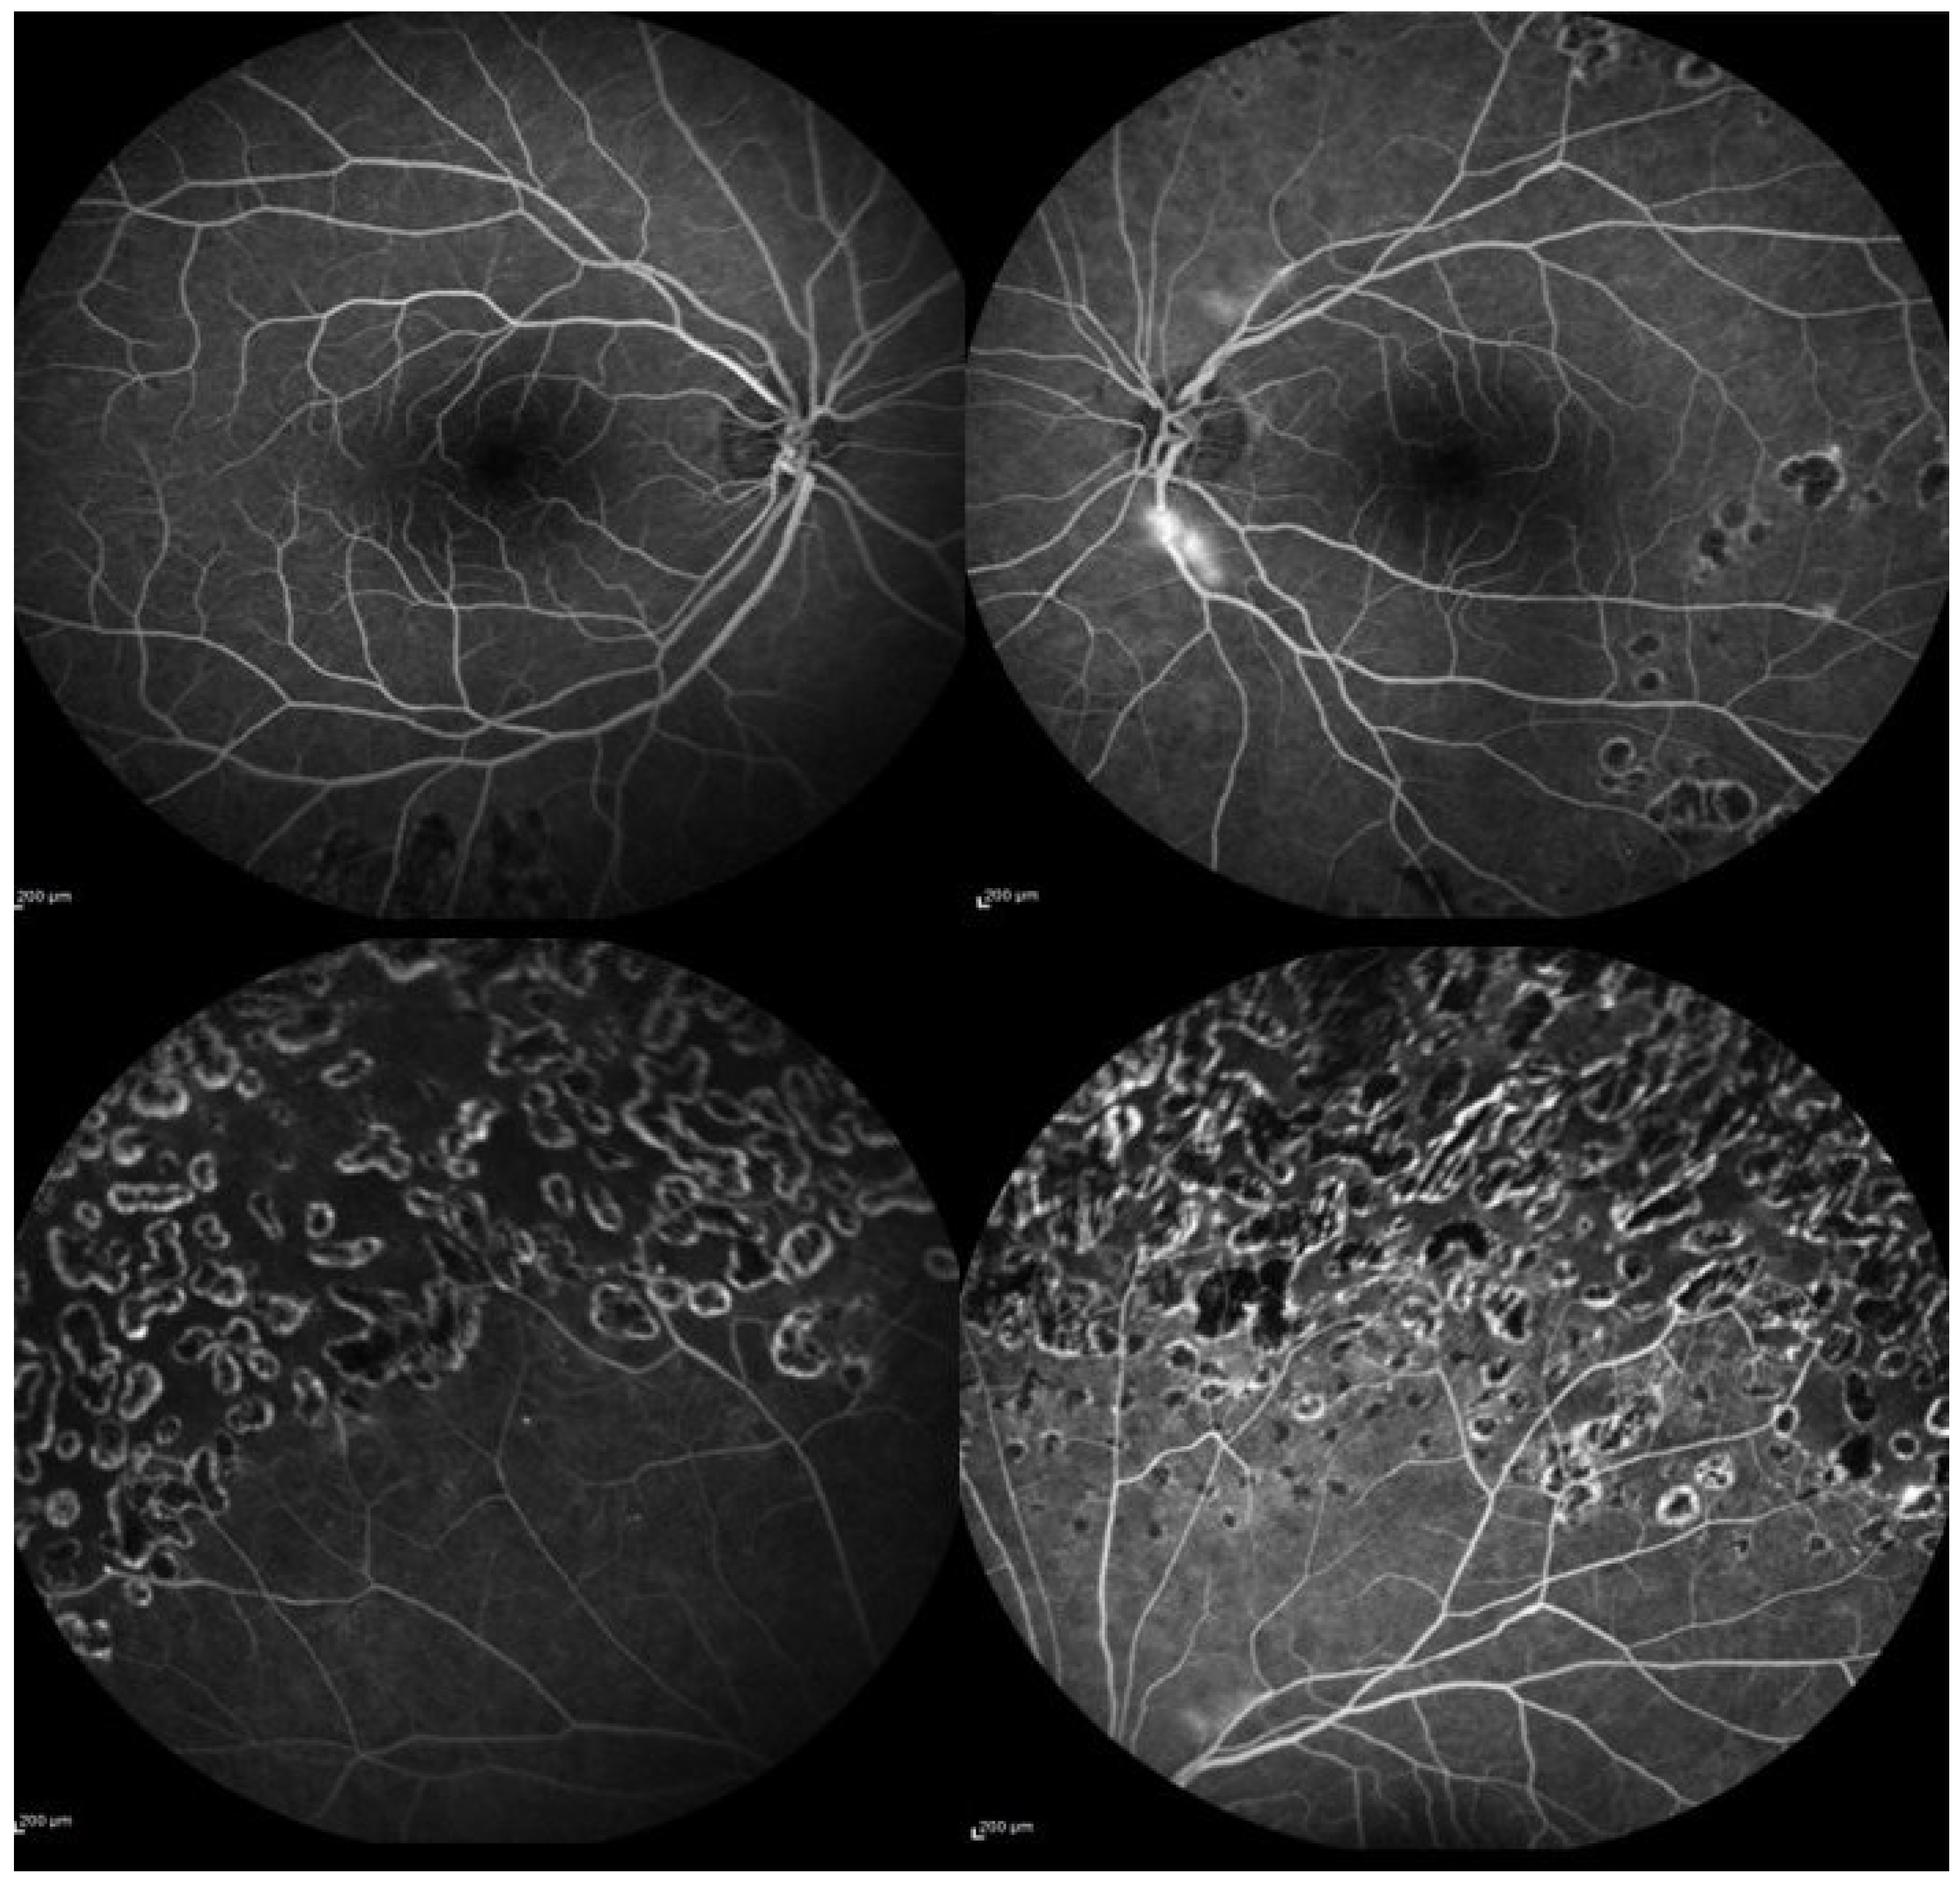

2. Case Presentation